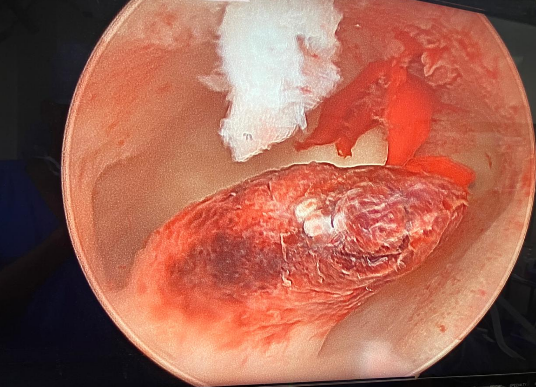

Women’s health requires a thoughtful and personalized approach at every stage of life. Our gynecology services are designed to diagnose, manage, and treat a wide range of gynecological conditions with accuracy, compassion, and advanced medical expertise. We provide comprehensive care for issues such as menstrual irregularities, pelvic pain, hormonal imbalances, reproductive health concerns, infections, fibroids, ovarian cysts, and other common and complex gynecological conditions.

Using modern diagnostic techniques and evidence-based treatments, our team focuses on identifying the root cause of symptoms rather than just managing them temporarily. Each patient receives an individualized treatment plan based on her medical history, symptoms, and overall health goals. From routine check-ups and preventive screenings to specialized treatments and minimally invasive procedures, we aim to deliver safe and effective care tailored to each individual.